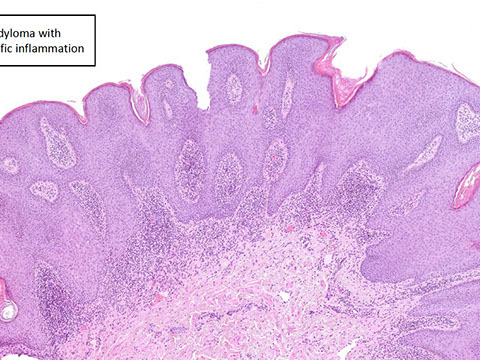

• Inflammatory polyps

• Pseudopolyps

• Filiform (postinflammatory) polyps